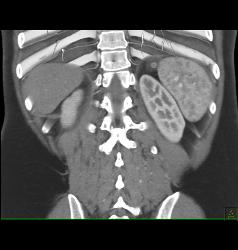

Diagnosis

Antral Carcinoma